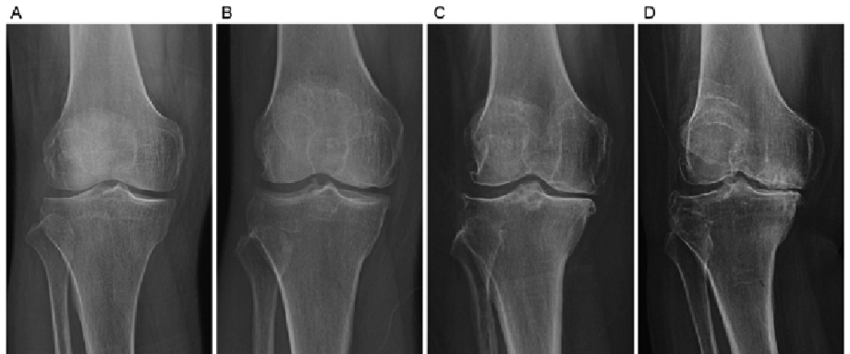

STAGING OF ARTHRITIS

Arthritis Stage 1

Arthritis Stage 2